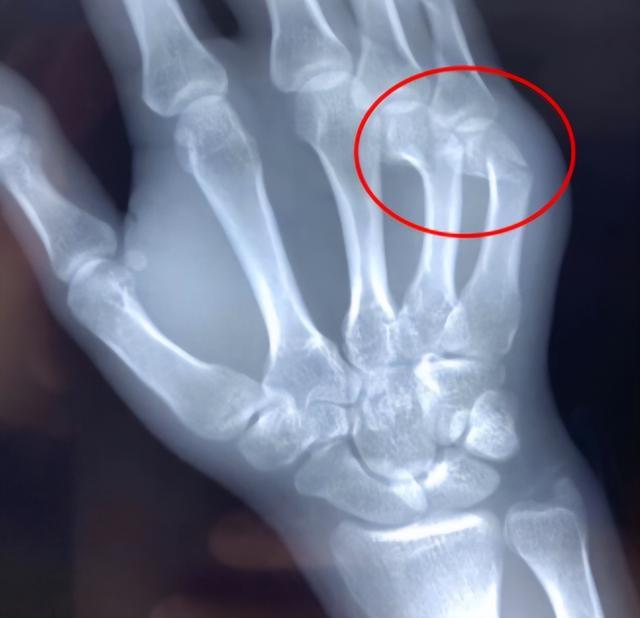

接诊的湖南旺旺医院骨科谢毅凌副主任医师给予右手X线检查,诊断为第4.5掌骨颈骨折,又称“拳击手骨折”,是在握拳状态下直接创伤所致。

(▲左侧第4.5掌骨颈骨折,错位明显)